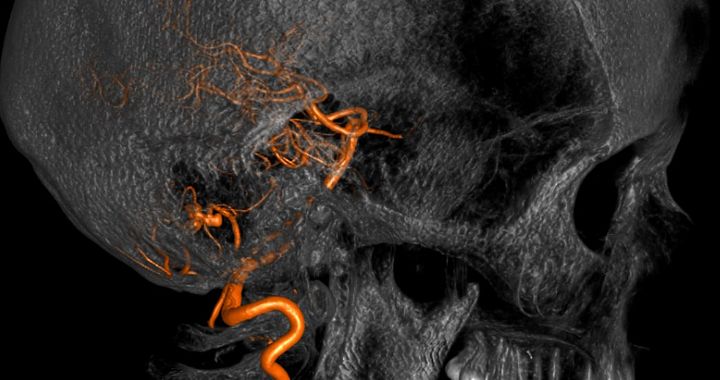

Aneurysmen

Aneurysmen sind Gefäßaussackungen an hirnversorgenden Arterien, die sich häufig im Bereich der Verzweigungen von Hirnbasisarterien befinden. Im Laufe der Zeit können diese Aneurysmen an Größe zunehmen (wachsen) und durch Druck auf Gehirn bzw. Hirnnerven zu neurologischen Symptomen führen. Kommt es zu einer Ruptur („Platzen“) des Aneurysmas, liegt eine lebensbedrohliche Notfallsituation vor und die daraus resultierende Hirnblutung (Subarachnoidalblutung) endet nicht selten tödlich oder führt zu schwerer Behinderung mit lebenslanger Pflegebedürftigkeit.

Ein Aneurysma, das bereits geblutet hat, sollte genau wie ein Aneurysma, das Beschwerden hervorruft und solche, die mit der Zeit eine Wachstumstendenz zeigen, behandelt werden. Bei zufällig entdeckten Aneurysmen muss man die Risiken des Aneurysmas gegen die der Behandlung abwägen. Um eine Blutung oder eine erneute Blutung zu verhindern, muss das Aneurysma von der Blutversorgung „abgeschnitten“ bzw. „ausgeschaltet“ werden. Dies kann erreicht werden, indem in mikrochirurgischer Technik der knöcherne Schädel und die Hirnhäute eröffnet werden und von außen ein Titan-Clip auf den Hals des Aneurysmas gesetzt und so die Verbindung zum Blutgefäßsystem unterbunden wird. Diese Methode nennt man operatives Clipping.

Eine andere Möglichkeit ist die sogenannte endovaskuläre Coil-Embolisation, eine Intervention durch die Abteilung für Neuroradiologie, bei dem das Aneurysma mittels eines Katheters über die Leistenarterie von innen mit Platinspiralen ausgefüllt wird. Erscheint eine Behandlung nicht sinnvoll, muss die Form und Größe des Aneurysmas regelmäßig durch bildgebende Untersuchungen kontrolliert werden.